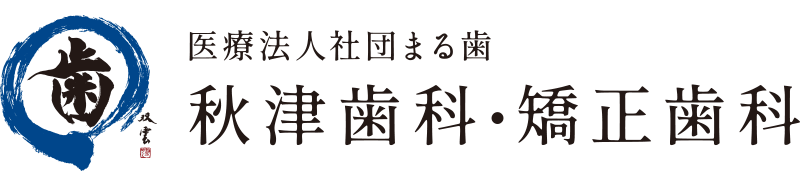

ケース1

| 年齢・性別 | 64歳・男性 |

| 主 訴 | 虫歯が深く保存不可のため、インプラント治療を検討 |

| 治療部位 | 右下5番6番 |

| 治療期間 | 8~9ヶ月 |

| 治療費 | インプラント埋入:165,000円×2 GBR:110,000円×2 FGG:110,000円 インプラントTEK(仮歯):55,000円インプラント×2 上部構造(ジルコニアステインクラウン):165,000円×2 サージカルガイド:66,000円 合計:1,166,000円 (2021年11月現在) |

| 治療内容 | 右下5番6番 インプラント埋入、GBR、FGG、インプラントTEK、インプラント上部構造(ジルコニアステインクラウン)、サージカルガイド |

| 治療の リスク |

術後腫れる、痛む可能性がある。インプラント自体は虫歯にはならないが、歯周病になる可能性がある。 インプラントと骨が結合しない場合がある。 FGG 出血が止まりにくいことがあります。移植した歯肉が生着しないことがあります。 |

| 治療方針 | 虫歯が進行し保存不可になった歯を抜歯し、傷の治りを待ってインプラント治療を行いました。 インプラントを埋入するのに必要な骨の厚みを得るため、骨の造成も行いました。 |

| 特記事項 | 骨造成を行ったので、インプラント体が結合するのに時間がかかりました。 その間は他の虫歯治療を並行し進め、クリーニングを定期的に行うことで清潔な状態をキープしました。 |

| メンテナンス担当者所見 | 治療後、快適に長持ちさせるために定期的なメンテナンスの必要性と、患者さま自身による毎日の正しい口内清掃の重要性を御理解いただきました。 |